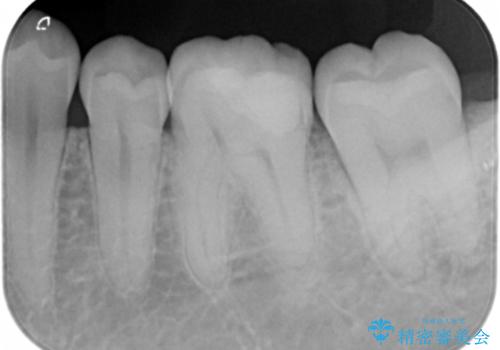

- 他院で入れたセラミックインレーが欠けてしまい来院。

→欠けたところが上の歯と噛み込んでおり、そのままやりかえるとさらに歯が薄くなり、また欠けてしまうリスクが高い状態

②ゴールドアンレーに変更する

→欠けた部分をしっかり覆うことができる。薄い歯質の部分がなくなり、歯は割れにくくなる。

欠けてしまったところを放置すると、歯と詰め物の隙間から細菌が溜まり、虫歯の再発のリスクが高まります。